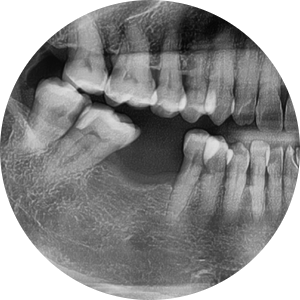

내원 당시 초진 엑스레이 사진

“예전에 뽑았던 어금니 자리, 요즘 들어 더 불편하고 음식도 잘 안 씹힌다”며 내원하셨습니다.

50대 외국인 여성분께서 내원해주셨는데,

파노라마 촬영 결과, 오른쪽 아래 첫 번째 어금니발치

상태로 방치되어 있었고, 양 옆 치아가 살짝 쓰러지기 시작한 모습이 보였습니다.